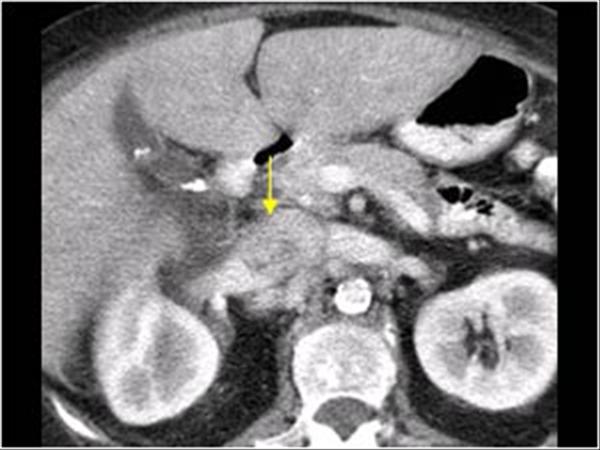

# Ung thư biểu mô tế bào thận phải (Renal cell carcinoma – RCC) / Huyết khối tĩnh mạch chủ dưới.